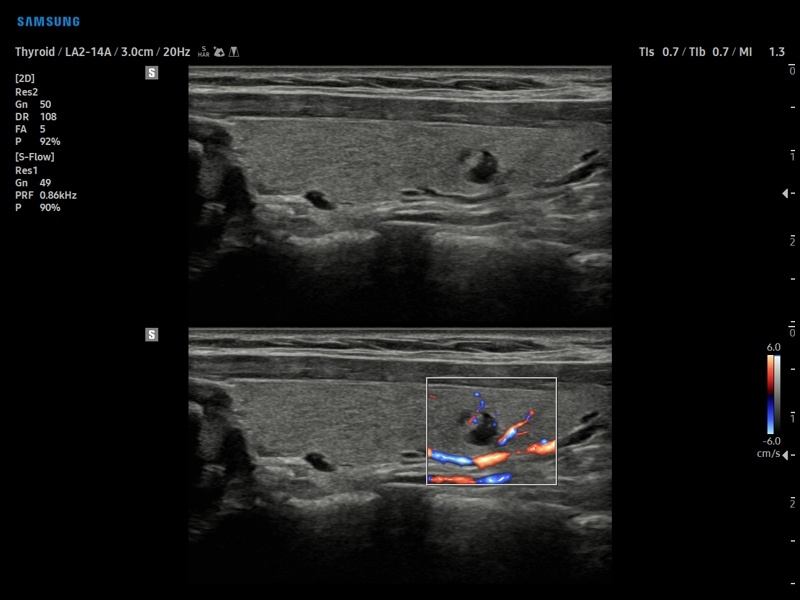

• S-Detect для исследования молочной железы и щитовидной железы

• Исследования поверхностных органов

• МодульS-Detect Breast- программа автоматического обнаружения и анализа образований молочной железы у женщин, измерение и классификация по системе BI-RADS.

• МодульS-Detect Thyroid- программа автоматического обнаружения образований и анализа щитовидной железы, измерение и классификация по системе системе TI-RADS.

• Модуль S-Detect Breast - программа автоматического обнаружения и анализа образований молочной железы у женщин, измерение и классификация по системе BI-RADS.

• Модуль S-Detect Thyroid - программа автоматического обнаружения образований и анализа щитовидной железы, измерение и классификация по системе системе TI-RADS.